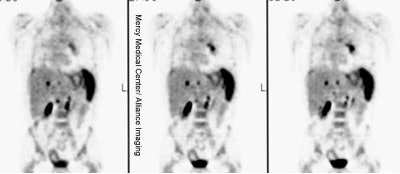

Monitor response to therapy in lymphoma: The patient shown below was a 29 year old male with a history of recurrent lymphoma despite chemotherapy and stem cell transplant. The patients initial PET scan (left) demonstrated extensive nodal disease throughtout the neck, chest, abdomen, and pelvis. The patient was treated with a repeat stem cell transplant. A post-treatment FDG PET exam demonstrated interval resolution of previously identified sites of disease consistent with a response to therapy. Note renal collecting system activity on both studies. The exams were performed on a Siemens ECAT EXACT PET scanner (manufactured by CTI). Case courtesy of North Texas Clinical PET Institute, Dallas, Texas and CTI PET Systems, Inc. Click images to view cine avi file (230K) |

|

Monitor response to therapy in lymphoma: The patient shown below is a teenage male with Hodgkins disease. The pre-therapy scan confirmed disease only above the diaphragm. The post-therapy scan was performed following two cycles of chemotherapy and demonstrated complete resolution of all sites of disease. Early data indicates that following effective chemotherapy, there is a rapid decrease in metabolic activity within the tumor. Click images to view rotating avi files (note para-cardiac and costophrenic angle nodes can also be seen on these images). |